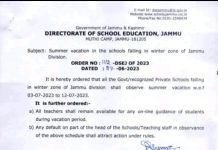

Himachal Pradesh: Eight spoons, two screwdrivers, two toothbrushes and a knife that were recovered from a mentally ill man in Mandi district of Himachal Pradesh.The patient’s abdominal X-ray shows the cutlery he had ingested.

Sen’s X- ray and Radiography revealed that he had several foreign items inside his stomach.